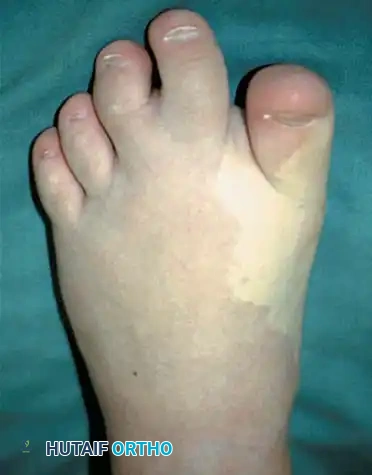

Fig. 26-5 A, Macrodactyly in 2-year-old child with Klippel-Trenaunay-Weber syndrome.

Fig. 26-5 C, Clinical appearance of macrodactyly in another child.